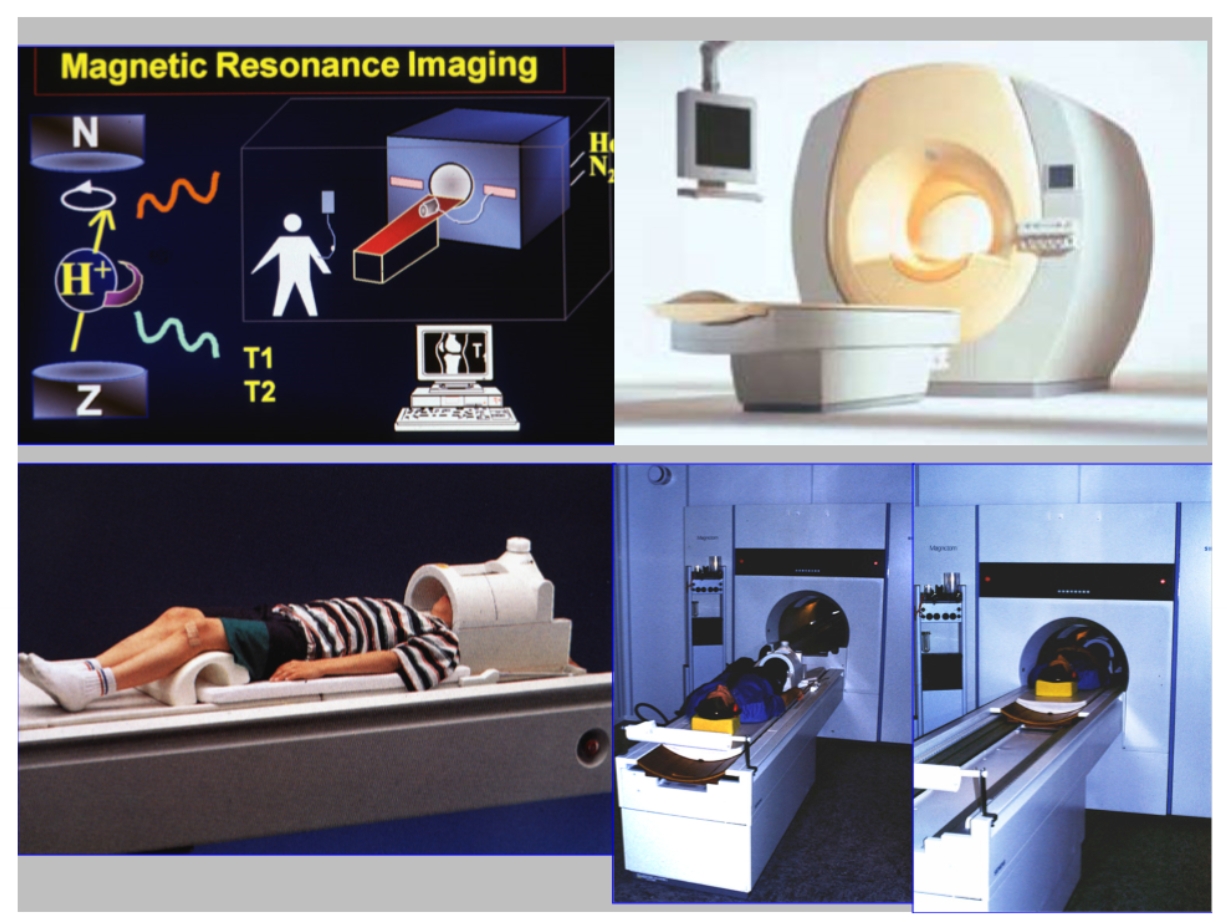

MRI

= magnetische resonantie

werkt met magneetvelden & radiogolven → dus niet met röntgenstralen

2 soorten MRI-beelden

T1-beeld

water & CSV (cerebrospinaal vocht) = donkergrijs

T2-beeld

water (en CSV) = wit

(WWW)